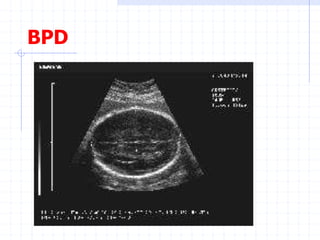

Assessment of fetal growth by

Biometry:

BPD

BPD & HC